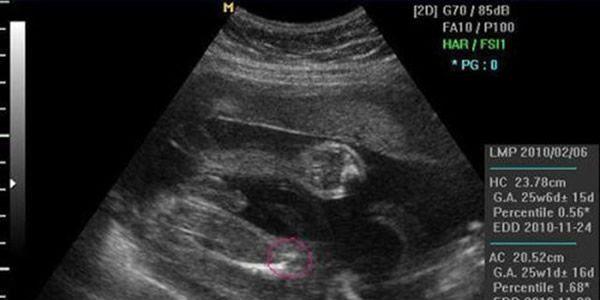

NT检查的时候是看不到这些类似于胎儿生殖特点的,因为NT检查在11-13周进行,这个孕周胎儿宝宝还太小,外生殖器也还未正式开始发育。通过NT检查看胎儿双腿间的亮点和白线进行性别判断并没有科学依据。

一般在4个月左右医生可以通过B超明确胎儿性别的。但是要看胎位情况,胎位好看时就准确,但不要太过相信判断。对于判断胎儿的性别来说,最直观的方法就是B超,B超下可以清晰的看清楚胎儿的各个器官和部位,包括生殖器。但是目前我们国家法律上规定,是不能擅自告诉孕妇胎儿的性别的,是属于违法的。